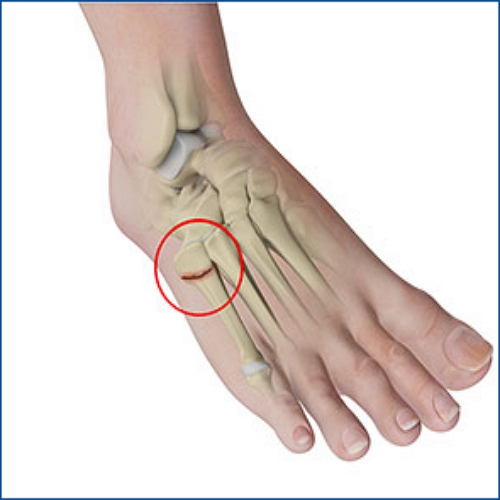

발등 피로골절 증상과 치료법

발등 피로골절은 발의 중간 부위인 중족골에서 발생하는 작은 균열로, 주로 장기간 서 있기, 달리기, 뛰기 또는 무거운 물건을 자주 드는 활동 등 발에 지속적인 압력이 가해질 때 발생합니다. 이러한 유형의 골절은 초기에는 증상이 경미하여 간과하기 쉬우나, 적절히 치료하지 않으면 통증이 악화되고 회복 시간이 길어질 수 있습니다.

발등 피로골절의 진단

- 증상 확인: 피로골절의 가장 흔한 증상은 활동 중 또는 그 이후에 발등에서 느껴지는 통증입니다. 통증은 초기에는 활동을 할 때만 나타나지만, 시간이 지날수록 지속적으로 느껴질 수 있습니다.

- 물리적 검사: 의사는 발의 부기, 발적, 압통 또는 변형을 확인하기 위해 발을 직접 검사합니다.

- 영상 진단: X-레이, MRI 또는 CT 스캔을 통해 발등의 피로골절을 확인할 수 있습니다. X-레이는 초기에는 골절을 나타내지 않을 수 있으므로, 증상이 지속되면 추가적인 MRI 또는 CT 스캔이 필요할 수 있습니다.